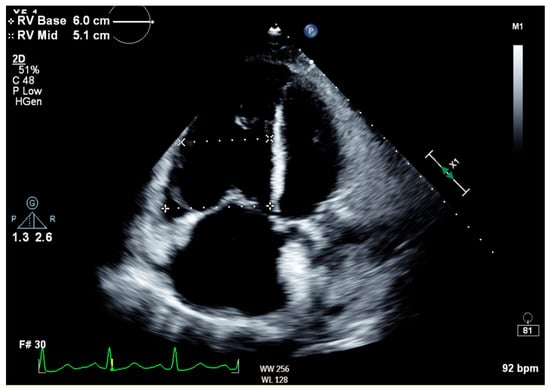

Notable normal admitting lab values included the following: aspartate aminotransferase, alanine transaminase, alkaline phosphatase, bilirubin, platelet count, and international normalized ratio. Creatinine on arrival was 0.79 mg/dL and white blood cell count was 6.0 cells/μL. The only noteworthy abnormal lab was an elevated brain natriuretic peptide of 864 pg/mL. Venous blood gas on arrival with pH of 7.353, pCO2 55.9 mmHg, HCO3 31.1 mmHg, and pO2 21 mmHg. Large-volume paracentesis was performed (5 L), with fluid analysis revealing a serum–ascites albumin gradient (SAAG) of 1.2 g/dL and total protein of 2.6 g/dL. The total nucleated cell count was 1020 cells/mm3 with a polymorphic nucleated cell count (PMN) of 663 cells/mm3, consistent with SBP. The bacterial culture of peritoneal fluid did not grow any organism. An abdominal ultrasound revealed nodular contours within the liver and heterogeneous echotexture compatible with cirrhosis (Figure 1). Doppler imaging of the liver showed patent vessels. Repeat TTE on this admission showed a preserved EF of 65% with paradoxical septal motion, flattened interventricular septum, and severe right ventricular (RV) enlargement consistent with RV pressure/volume overload. The pulmonary systolic pressure was estimated at 74 mmHg (Figure 2). Additionally, the patient was found to have moderate tricuspid regurgitation with a maximum velocity of 385 cm/second (Figure 3).

Figure 2. Transthoracic echocardiogram in apical four-chamber view showing severe right atrial and ventricular enlargement, as well as flattened interventricular septum, consistent with elevated RV pressure and volume overload.